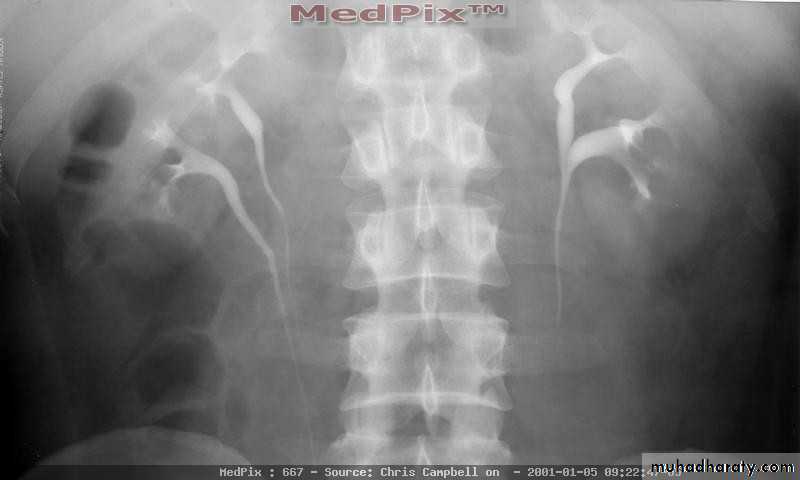

Found in 1:1000 necropsies and is more common in men.probably the most common of all renal fusion anomalies

The anomaly consists of two distinct renal masses lying vertically on either side of the midline and connected at their respective lower poles by a parenchymatous or fibrous isthmus that crosses the midplane of the body.

Fusion of the renal masses occurs early in embryonic life, so its ascent will be impeded by inferior mesenteric artery.

The kidneys are low located, mal rotated and pelves lie anteriorly

Diagnosis ultrasound, IVU, CT scan